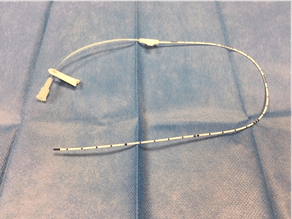

El tipo de líneas medias insertadas son las siguientes:

Mini-midline

- Catéter periférico largo de poliuretano

- Calibre :18 G

- Longitud :10 cm

- Técnica de inserción: Seldinger directa o mediante dispositivo integrado todo en uno

- Ubicación punta de catéter en trayecto braquial de vena axilar.

- Duración: 1 mes

Midline medioclavicular

- Catéter periférico largo de poliuretano de 3ª generación

- Calibre 4 Fr

- Longitud: 20 – 30 cm

- Técnica de inserción: Seldinger modificada/directa

- Ubicación de punta de catéter en vena tramo torácico axilar o subclavia

- Duración: Meses

Nutriline (Vygon)